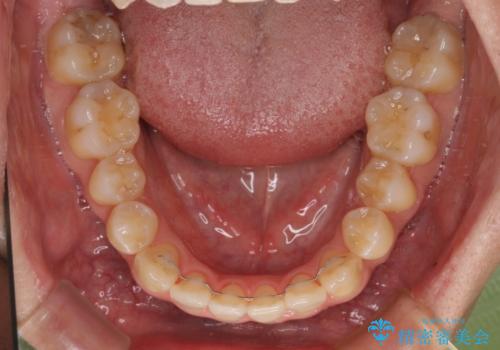

左右の八重歯が気になる ワイヤー装置での咬み合わせ改善

- 八重歯と前歯のデコボコを気にして来院された患者様です。

舌の突出癖がなかなか改善されず、上下前歯部の接触が得られるまでに予定の倍ほどの期間がかかりました。